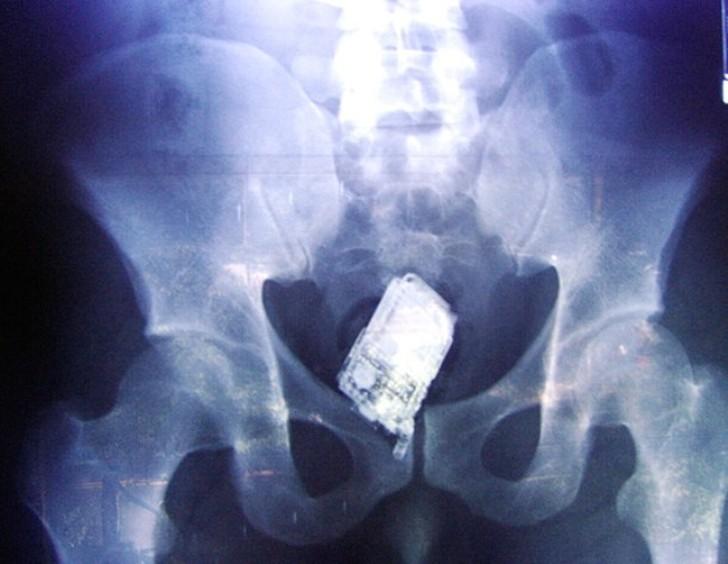

20. Мобильник.